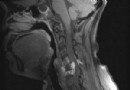

你好,這可能是心肌缺血所致。建議做一下64排CT檢查,看一下心髒血管的情況,看有沒有心肌橋